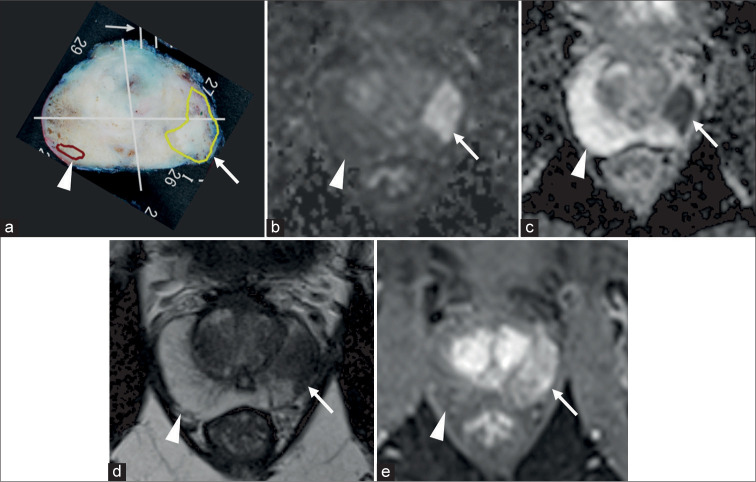

Abstract Image